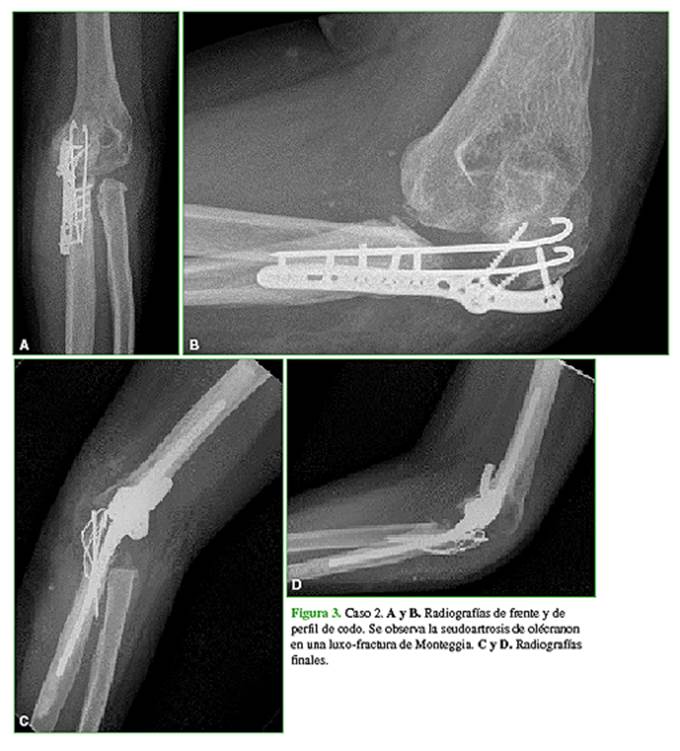

Hombre de 27 años que consultó por dolor e inestabilidad en el codo izquierdo. Como antecedentes presentaba una luxo-fractura de Monteggia de tres años de evolución, operada en cuatro oportunidades. En la primera cirugía, se le realizó la osteosíntesis del olécranon; luego, se le colocó un sistema de absorbe-tracción por subluxación, se resecó la cúpula radial y, por último, se extrajo toda la osteosíntesis. La flexo-extensión era de 110°-40°, con un puntaje de dolor de 5 en la EAV, un puntaje MEPS de 35 y un puntaje DASH de 46. Las radiografías mostraban el desgaste articular y la SO. Previa punción para descartar infección, el paciente fue operado con la técnica descrita. Se le colocó una prótesis de Coonrad-Morrey. A los cuatro años de seguimiento, la flexo-extensión era de 120°-35°, con un puntaje de 2 en la EAV, un puntaje MEPS de 75 y un puntaje DASH de 27. La seudoartrosis estaba consolidada y la prótesis no tenía signos de aflojamiento (Figura 3).